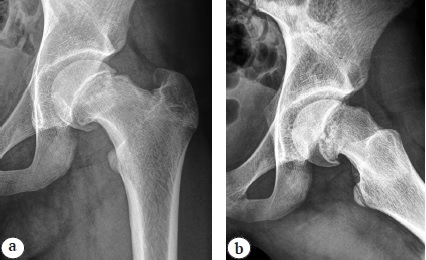

Рис. 2. Рентгенограммы правого тазобедренного сустава в переднезадней проекции (а) и в проекции Лауэнштейна (b) пациентки 14 лет 9 мес. перед операцией: отсутствие признаков синостозирования на уровне эпифизарной зоны роста, положительный симптом «сегмента», костный выступ на передней поверхности шейки бедренной кости

Угол смещения эпифиза кзади рассчитывался по разнице ЭУ в суставе без смещения (индивидуальная норма) и в суставе со смещением, угол смещения книзу — по разнице ШДУ и ЭДУ в суставе со смещением.